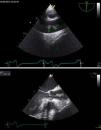

A 69-year-old man was admitted to the emergency room due to acute pulmonary edema. He had no known history of cardiovascular disease. The physical exam was notable for a harsh, grade IV/VI aortic systolic murmur and diffuse lung crackles. A transthoracic echocardiogram showed severe aortic stenosis, with normal biventricular systolic function. Coronary angiography was performed, as aortic valve surgery was envisioned. The next day the patient presented with fever and no other symptoms. Empirical antibiotic therapy was started. Blood cultures were drawn and methicillin-sensitive Staphylococcus aureus was identified, prompting a change in antibiotic therapy to vancomycin and gentamicin. Endocarditis was suspected and a transesophageal echocardiogram was performed. The exam showed a 14 mm pedunculated and highly mobile mass attached to the intima, protruding from the posterior wall of the ascending aorta, at the level of the sinotubular junction (Figures 1 and 2). Given the high embolic risk and to avoid the development of a mycotic aneurysm, the case was discussed with the cardiac surgeon and the patient was operated the next day. An inflamed ascending aorta was detected in the operating theater; the mass was excised and the ascending aorta and aortic valve were replaced. The histopathology was notable for aortic endarteritis, with granulocyte infiltration (Figure 3). After the operation, antibiotics were continued to complete an eight-week course. The patient was discharged thereafter. Our case illustrates a very rare location of a vegetation implanted in the aortic root, probably secondary to intimal trauma from prior coronary catheterization.